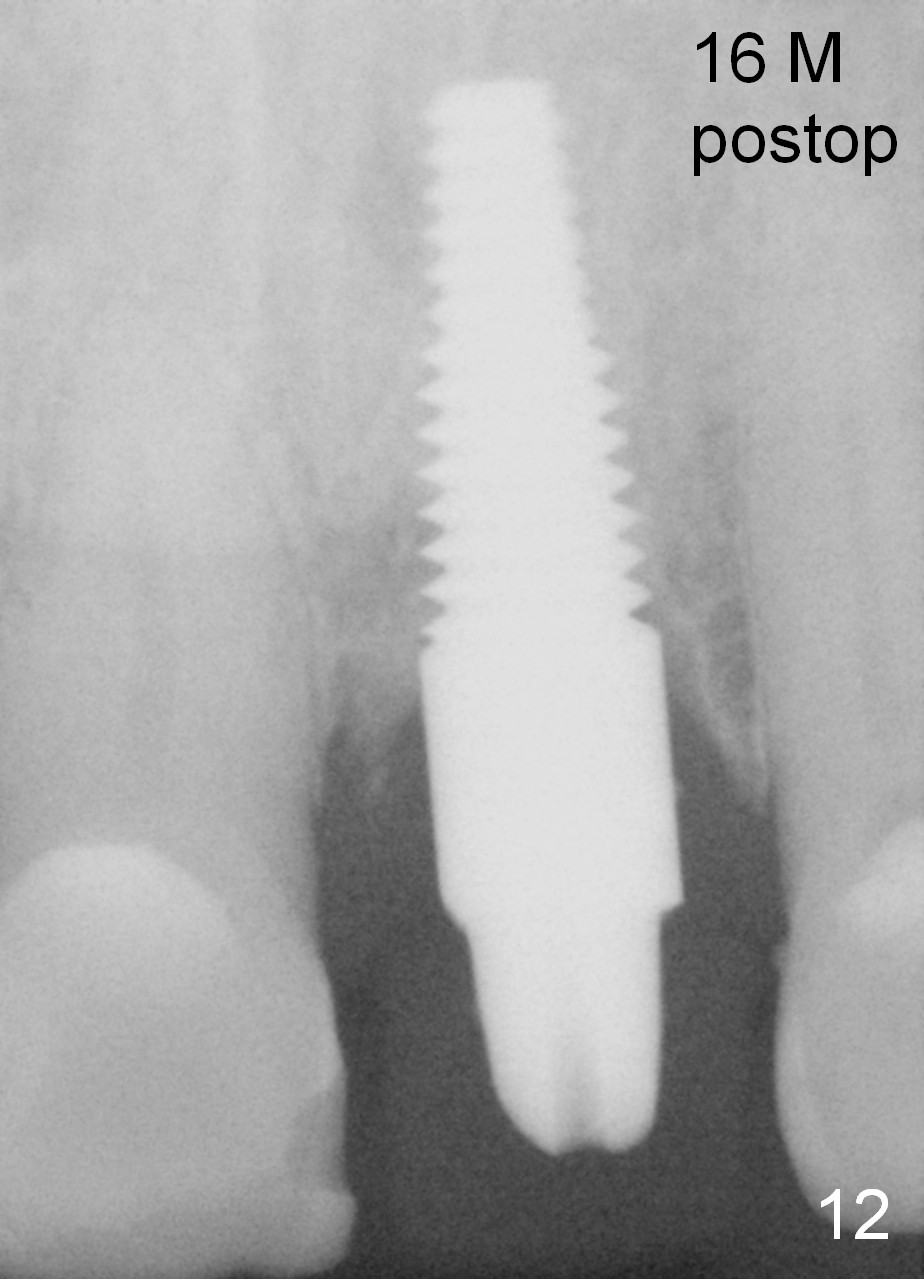

Fig.12: 16 months postop (before impression).